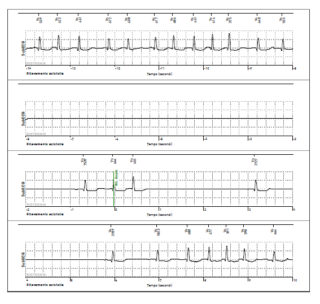

Le bradiaritmie sono disturbi cardiaci nei quali la frequenza cardiaca è più bassa del normale. Il danno che sottende a tale aritmia può essere localizzato al nodo del seno (la zona che genera il battito) o al nodo atrio-ventricolare (la regione che permette il transito dell’impulso elettrico dalle camere atriali a quelle ventricolari).

Le bradicardie sinusali comprendono quindi le varie forme di malattia del nodo sinusale e possono essere caratterizzate da un rallentamento generalizzato del battito o da un improvvisa assenza del battito stesso (nel primo caso si parla di bradicardia sinusale, nel secondo caso di arresto sinusale).

Anche in corso di fibrillazione atriale, sia nel corso dell’aritmia per un blocco della conduzione dell’impulsi a livello atrio-ventricolare, che al tentativo di recupero spontaneo del ritmo sinusale per la presenza di un arresto sinusale, possono occorrere pause anche molto prolungate.

I blocchi atrio-ventricolari (BAV) sono disturbi della conduzione dell’impulso elettrico a livello del nodo atrio-ventricolare. I blocchi atrio-ventricolari sono divisi in tre gradi:

• primo grado o conduzione rallentata, in cui tutti gli impulsi atriali sono condotti ai ventricoli con ritardo;

• secondo grado o conduzione intermittente, in cui alcuni impulsi sono condotti e altri bloccati;

• terzo grado o blocco completo, in cui nessun impulso atriale viene condotto ai ventricoli.